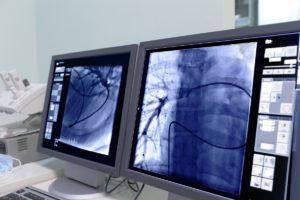

Контрастное вещество при коронарографии распределяется по всем венечным сосудам, и при помощи ангиографа можно на мониторе увидеть качество распределения и наполнения сосудов. Для составления полной картины проходимости коронарных сосудов снимки делаются со всех сторон.

- Фиксирование процесса ангиографом, просмотр происходящего на мониторе и запись результатов. Съемка артерий производится в нескольких проекциях и различных плоскостях.

Это рентгеновское исследование просвета коронарных сосудов при помощи ангиографа и контрастного вещества, введенного через катетер именно в преддверие сердечных артерий. Съемка проводится под разными ракурсами, что позволяет создать наиболее подробную картинку состояния объекта обследования.

По сосудам катетер под контролем ангиографа проводят до устья коронарных артерий. Поочередно в каждую из них вводят контрастное вещество, которое и обрисовывает внутреннее пространство этих сосудов. Проводится съемка и фиксация с разных положений. Определяется место стеноза или окклюзии.